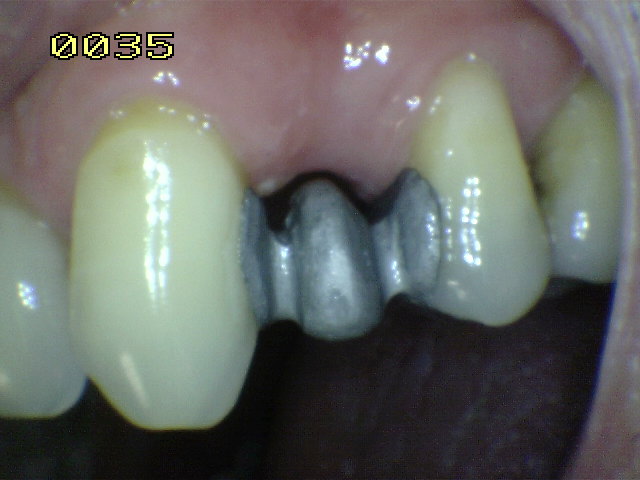

Cemento de resina  adherido al metal

Cemento de resina  adherido al metal. Se ha utilizado el grabado electrolítico en acido sulfúrico, por ello se observa la tenáz adhesión al metal